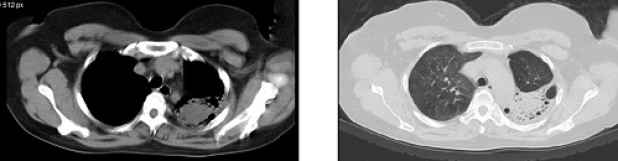

Se evalúa el caso teniendo en cuenta los valores de tiroglobulina, y ante la sospecha de un falso positivo se complementa el estudio con radiografía de tórax (fig. 4) y tomografía computada de tórax sin contraste (figs. 5 y 6), evidenciándose una lesión focal nodular en segmentos 1 y 2 del pulmón izquierdo de 42 mm de diámetro, con tractos fibrosos y bronquiectasias adyacentes. El primer planteo diagnóstico es de un aspergiloma, sin descartar proceso neoproliferativo primario.